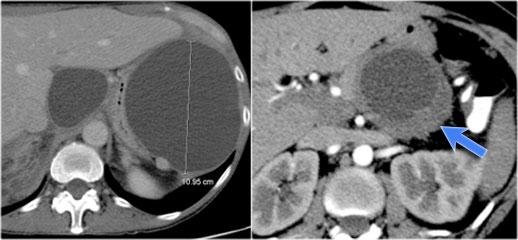

Hình ảnh CT cho thấy một nang lớn ở vùng thượng vị trên bệnh nhân có tiền sử viêm tụy cấp (Hình).

Lưu ý có thêm một ít dịch cổ trướng và dịch màng phổi.

Thành nang có ngấm thuốc.

CT cho thấy hai nang lớn ở bệnh nhân nữ 45 tuổi có tiền sử chấn thương (hình).

Lưu ý hình ảnh thâm nhiễm mỡ trong khoang sau phúc mạc (mũi tên).

Kết hợp đặc điểm hình ảnh với tiền sử lâm sàng, rất có khả năng đây là các nang giả tụy do chấn thương.